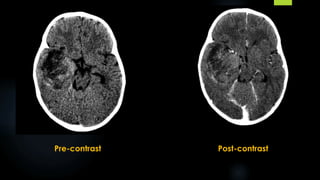

Medulloblastoma (contd.)

 CT - a heart or pear shaped hyperdense midline vermian mass abutting the roof of the fourth

ventricle, with perilesional oedema, variable patchy enhancement and hydrocephalus.

 Brainstem -displaced anteriorly.

 Cystic change, haemorrhage and calcification may be seen.

 Typical features - seen in only 30 % of cases

 Atypical features are common

- Cystic changes (65%)

- Isodense attenuation on NECT (3%) and abnormal contrast enhancement

Non Contrast Post contrast

 MRI:

 Hypointense on T1

 Variable hypo‐ to hyperintense on T2

 Variable enhancement

 restricted diffusion on diffusion-weighted imaging

T1

T1 + C

FLAIR

Gradient Echo DWI